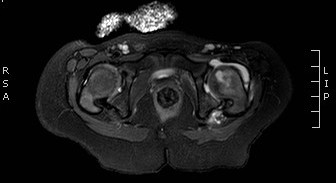

39.b.

39. a-b.MRI, T2 weighted and T1 weighted, postcontrast axial images. Signal intensity increase and increased contrast enhancement in the bone marrow of the left femoral neck,. 2 years old child, osteomyelitis. (with the courtesy of dr. Gábor Rudas).